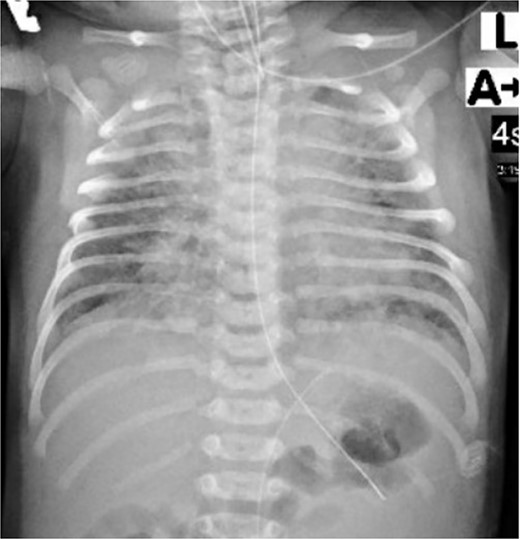

The infant was kept on mechanical ventilation for 9 h and then required oxygen supplement by nasal cannula for 6 days and finally she was able to maintain oxygen saturation by self-breathing in room air. Her initial chest X-ray (Fig. 5) showed diffuse patchy pulmonary infiltrations, which was improved on the following days. The infant was fully recovered and discharged home after 7 days. The infant was seen in pediatric clinic and the last follow-up visit was after three months revealed her growth and development within the expected normal level.

Chest X-ray of the neonate showed diffuse patchy pulmonary infiltrations.